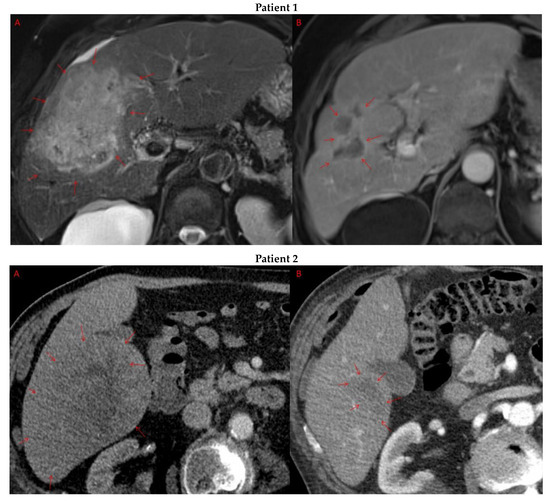

Pre- and post-treatment imaging for all exceptional responders is provided (Figure 3).

Figure 3.

Imaging findings in patients (n = 11) with complete response to neoadjuvant immunotherapy. Cross-sectional imaging for each patient with complete response to immunotherapy. Images represent the scan most recently taken prior to beginning the course of neoadjuvant treatment and the scan taken most recently after completion. (Patient 1) MRI showing large pre-treatment infiltrative tumor (A) followed by decrease in size from 10 cm to 5.6 cm status post 15 cycles of immunotherapy (B). (Patient 2) Large ill-defined 11cm tumor at diagnosis (A) followed by decrease in size to 3.6cm after 1 cycle Atezolizumab (B). (Patient 3) 13.3 cm mass with periportal lymphadenopathy (A) and subsequent decrease in size to 6.9 cm after 5 cycles of immunotherapy+1 round Y90 (B). (Patient 4) 8.1 cm mass in segment VIII with extension to right hepatic vein (A,B), and post-treatment tumor shrinkage after 11 cycles immunotherapy and locoregional treatment (C). (Patient 5) Recurrent scattered HCC lesions after previous resection (A–C). Near complete resolution after 4 cycles of immunotherapy and 1 Y90 (D,E). (Patient 6) 8 cm mass in segment II/III with portal vein invasion (A,B) and complete resolution after 22 cycles immunotherapy, Y90 and SBRT (C). (Patient 7) Infiltrative 20.3 cm mass in the left lobe with extensive tumor-in-vein in portal venous system (A,B) followed by complete resolution on 20 cycles immunotherapy, locoregional treatment and SBRT (C). (Patient 8). 7.1 cm mass in the right lobe (A,B) with reduction to 1.7 cm after 31 cycles immunotherapy (C). (Patient 9) 14.7 cm mass in the right hepatic lobe (A,B) shrinking to 5.8 cm after treatment (C,D). (Patient 10) Patient post-partial resection of segment IV/V for HCC with recurrence demonstrating 3.2 cm segment V/VIII lesion (A), a 4 cm lesion in the Right lower lobe (B) and a peritoneal metastasis (C). After treatment with 9 cycles immunotherapy + multiply Y90 treatments tumor size shrunk significantly (D–F). (Patient 11) Patient post-right hepatectomy for HCC with multiple diffuse recurrent nodules in the liver with largest measuring 2.6 cm (A,B). Post treatment imaging showing no evidence of disease (C).